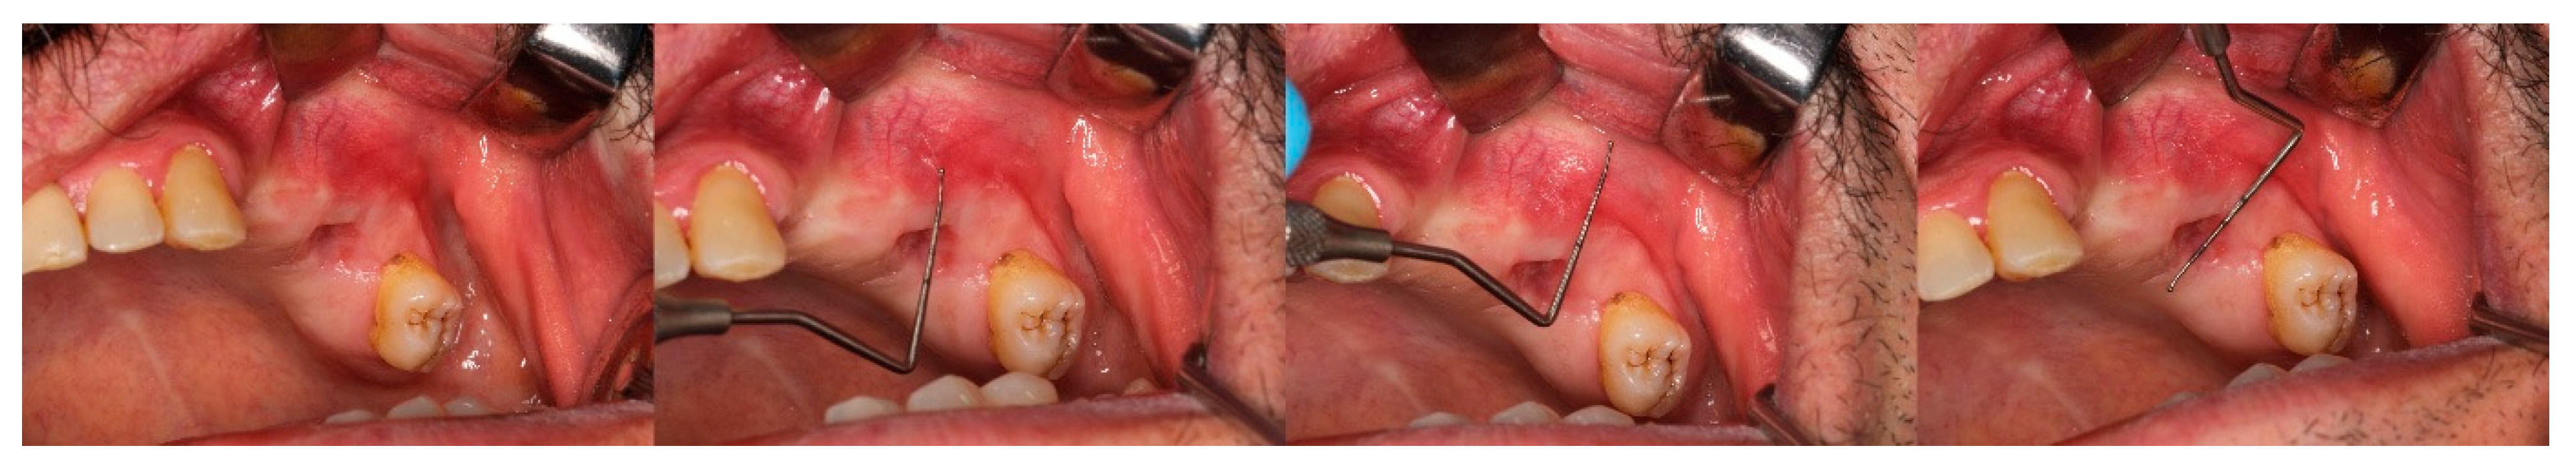

Figure 4. Measurement of the keratinised gingiva width, vestibular depth, and alveolar socket width on the 14th.

Figure 5. Measurements of the keratinised gingiva width, vestibular depth, and alveolar socket width on day 90.